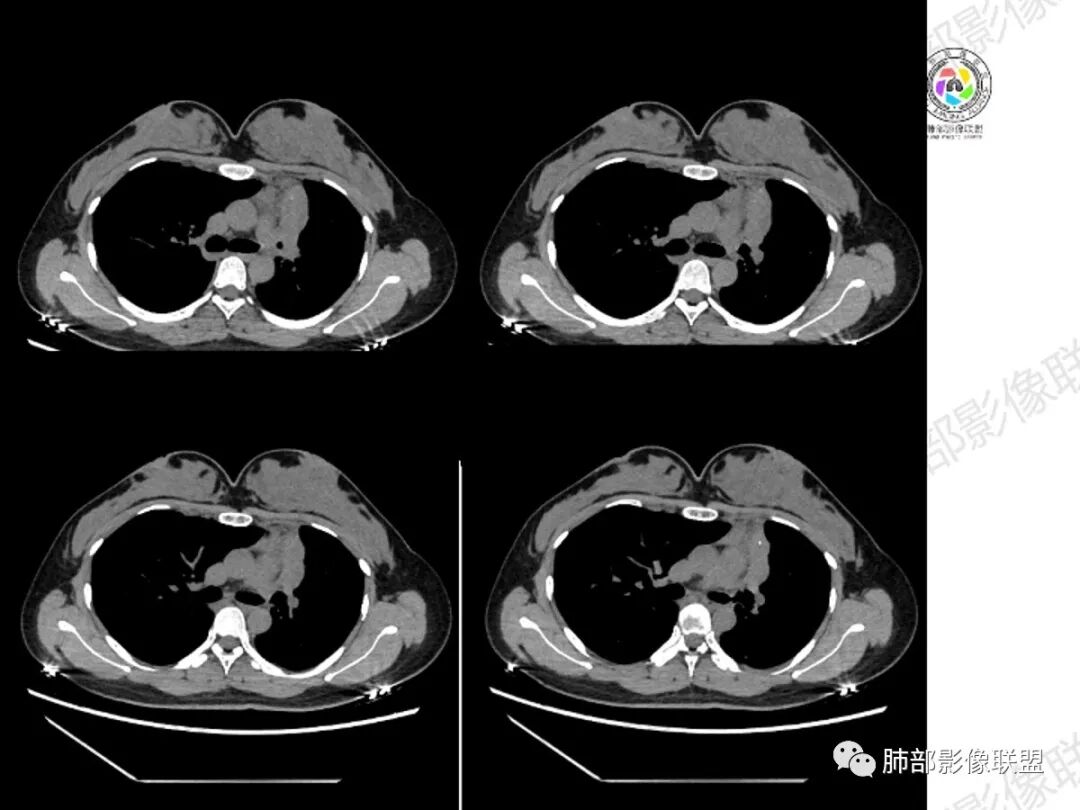

胸部CT:左肺体积缩小,左肺上叶前段纵隔旁胸膜下大片实变影,边缘清楚、匀齐、平直收缩,部分略膨隆,周围多发结节、树芽卫星灶,纵隔窗病灶与纵隔胸膜黏连,实变内多发点状钙化。平扫密度尚均匀,增强扫描不均匀明显强化,多个低密度区,呈仙人掌样,伴有条状血管影,考虑慢性炎症伴左上叶前段支气管闭塞,TB?鉴别黏表、腺癌等。

年轻女性,咳嗽咳痰一个月,左肺体积缩小,左肺尖部胸膜下实变影,宽基底与胸膜相贴,病灶边缘平直收缩,部分略膨隆,病灶下方可见支气管挤压,肺窗所示:周围伴有多发结节部分可见树丫征,纵隔窗可见病灶与纵隔胸膜黏连,部分与左肺动脉分界欠清,平扫密度尚均匀,增强扫描不均匀强化,内部可见多个低密度坏死,伴有条状血管影,纵隔淋巴结略有肿大。

女性,29岁,咳嗽咳痰,痰中带血1月余,CT示左肺尖胸膜下纵隔旁不规则实变影,内部可见小点状钙化灶,支气管略狭窄,增强可见低密度不强化区,粘液栓?实性成分明显不均匀强化,局部与左肺动脉分界不清,另左肺可见多发小结节,考虑为恶性,黏表可能,鉴别结核

年轻女性,咳嗦咳痰伴咳血1月多,ct可见纵隔左移,左肺容积减小,左肺上叶可见一不规则实变影,朝肺内侧边界清楚,部分边缘与纵隔界限模糊,临近支气管堵塞,内见点状钙化,增强不均匀强化,内可见多个低密度区,粘液?并与左肺动脉界限模糊,似受侵,考虑恶性,黏表?但病灶远端有多发小结节,卫星灶?结核待排